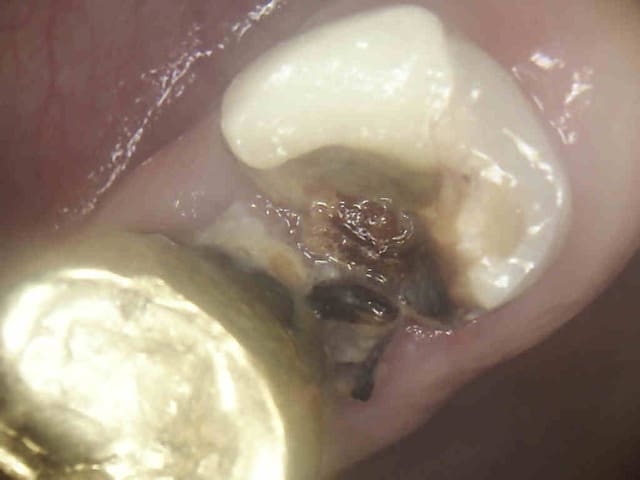

Souvent il n'y a rien, c'est plus facile. On peut d'ailleurs illustrer en quasi direct ses propos tellement c'est fréquent. Cas tous frais.-)))))

chicot,sauf ton respect tes preparation d entrée de canaux ne sont pas tres jolies .

a la turbine se serait plus lisse ,un meilleur parage cavitaire .moins sauvage en fait.en meme temps en profiter pour nettoyer la merde dentinaire .

Ah ? on nettoie la merde dentinaire à la turbine maintenant ? c'est nouveau ?

Tu es sur que tu es dentiste ?

Il y a des abrutis qui ne mettent pas de cone, ou un micro cone pour faire joli dans un océan de pate d'obturation dure comme du béton. Et le cone il fond, pas la pate.